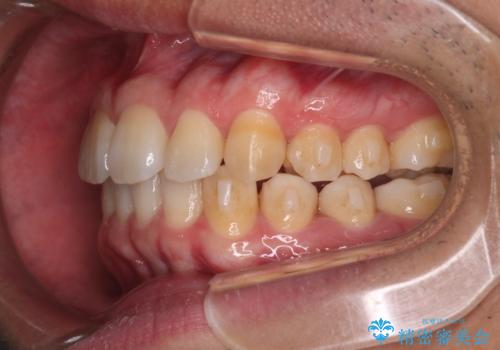

- 上の歯が出ているのが気になるのを主訴にご来院されました。人前で話すお仕事をされており目立たないマウスピース治療を希望されていました。

口元のEラインは気にならないとのことだったのでインビザラインにて治療していくことにしました。

IPR(歯と歯の間を削る処置)と歯列拡大をすることで前歯を少し下げ、がたつきを改善していく治療計画を立てました。

上の前歯が出ているという主訴が綺麗に改善されました。

その他の部位のがたつき、奥歯の噛み合わせも以前と比べると良くなっています。